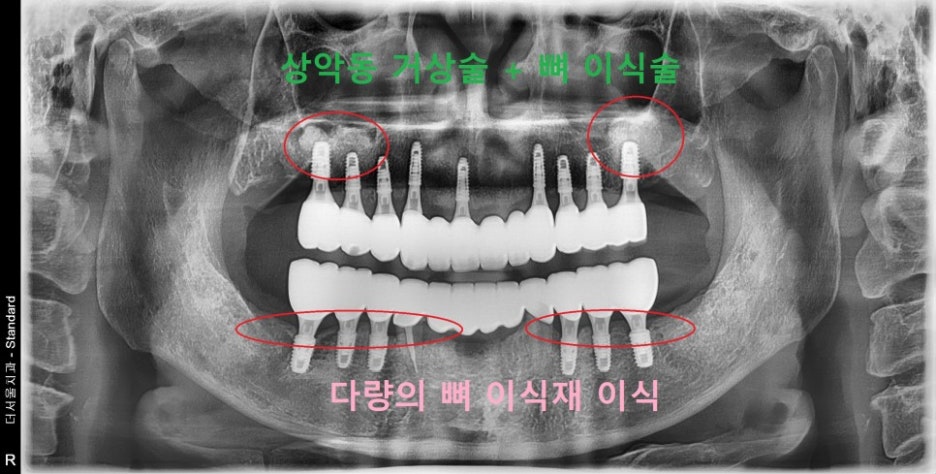

그렇다면, 이제는 잘 된 사례를 보여드립니다.

물론, 명의 라 불리는 제가 심었습니다.^^..

(깨알 자랑)

처음에 보여드렸던 사진과는 다른 모습을

볼 수 있습니다.

서로, 임플란트 끼리 수평한 기울기를

유지하고 있는 모습을 볼 수 있습니다.

물론, 해당 사진은 3년간의 f.u 을 담은 사진입니다.

주위염증도 없으면서 뼈의 높이 또한

잘 유지되고 있는 것을 보실 수 있습니다.